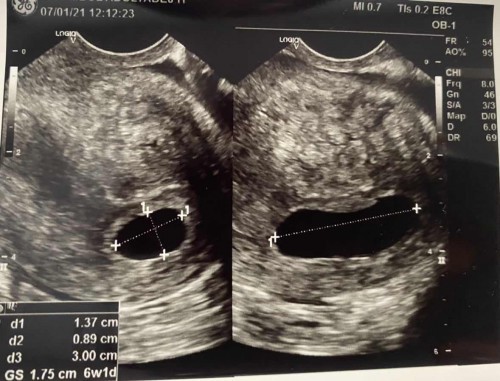

ฝากท้องครั้งแรก8wk(นับจากประจำเดือน) u/sผ่านช่องคลอด เจอถุงตั้งครรภ์แต่ยังไม่เจอตัว หมอบอกว่าจากU/Sแค่6wk อาจจะยังตัวเล็ก นัดอีกทีอาทิตย์หน้า หลังจากที่ไปฝากมา2วัน มีมูกสีน้ำตาลติดกกน. ทุกครั้งที่เข้าห้องน้ำเลยค่ะ แต่ไม่มีปวดท้อง ตอนนี้กลัวมากเลย 😢 มีโอกาสปกติอยู่มั้ยคะ

ตอน6วีค เจอแต่ถุงตังครรภ์เหมือนกันค่ะ ความยาวประมาณเซ็นครึ่ง ทางหน้าท้อง นัดซาวอีกทีตอน10สัปดาเจอทั้งตัวและหัวใจค่า ใจเย็นๆนะค่า